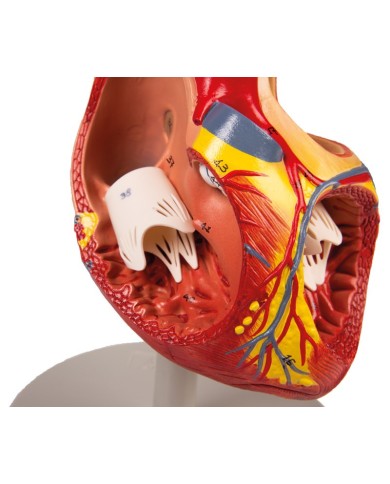

La parete anteriore del cuore è staccabile per poter vedere i ventricoli.

Realizzato in stampa 3D ad elevatissima risoluzione a colori.